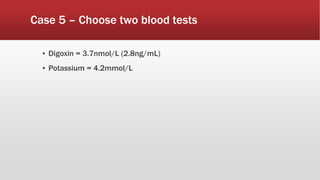

This document discusses various cases of collapse and syncope. It defines collapse as transient loss of consciousness with loss of postural tone and full recovery. Syncope is defined as loss of postural tone with or without loss of consciousness and full recovery. It then discusses the multiple potential causes of collapse and syncope including toxicological, cardiac conduction abnormalities, structural cardiac issues, autonomic dysfunction and more. It then goes through 9 case examples, discussing important questions to ask, potential tests and interventions for each case.